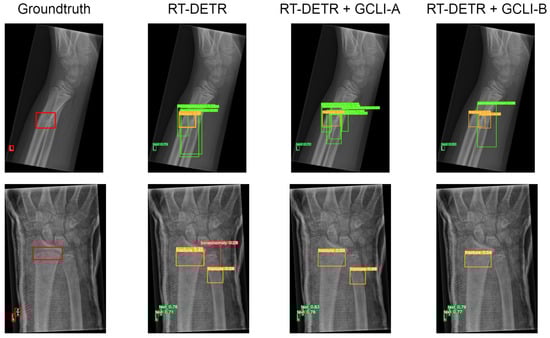

Further experiments are also carried out for object detection tasks with the aforementioned datasets. Table 9 illustrates the performance of RT-DETR and YOLOv8 with attention modules on the medium-scale VinDR-CXR dataset.

As Table 9 shows, with many overlapped objects on medical images, the architectures tend to perform worse. In terms of RT-DETR, only models with ECA, CBAM, and GCLI module A attached are able to surpass the baseline model. While ECA assists the model in reaching a higher mAP50, which is 10.3%, GCLI module A is able to increase the model’s recall, which is 27.9%. These two attention modules do not add much complexity to the models. However, GCLI module B is not the best option in the scenario of overlapped objects on medical images, as it only achieves 9.0% mAP50. In terms of YOLOv8, most of the attention modules tend to boost the performance of the architecture as they both reach higher performance compared to the baseline model. The GC block is the one that assists the model in achieving the highest mAP50 among attention modules in the category, which is 18.2%. However, this attention module introduces significant additional parameters to the architecture. Instead, our proposed GCLI modules A and B are able to boost the AP50 of YOLOv8 to 16.3% and 17.8%, respectively, resulting in GCLI module B standing in the second position of mAP50 without adding many extra parameters. From the results of the GCLI modules in both DL models, it can be concluded that under the effect of overlapping objects on medical images, GCLI modules may not be the best fit for handling this kind of noisy label. However, they can still increase model performance with a lower cost in complexity. Furthermore, the impact of attention modules varies depending on whether they are placed in the extraction or aggregation phases. In the extraction phase, GCLI module A typically outperforms GCLI module B and vice versa. Eventually, the partial attention strategy also indicates its benefits, especially if it is applied for the GCLI module that is placed at the aggregation phases rather than the extraction phases. Figure 14 and Figure 15 show the detection results for the baseline models RT-DETR and YOLOv8 as well as the changed version with our proposed GCLI modules attached. As illustrated, the proposed GCLI modules can address the problem of misleading objects better than the baseline models, introducing less redundant detection and providing higher precision performance.